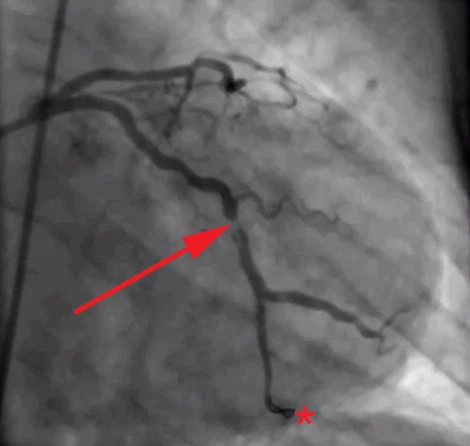

협심증, 심근경색을 진단하는 가장 정밀한 검사로 카테터라고 불리는 직경이 가는 플라스틱관(직경 2mm, 길이 약 1~2m)을 손목(요골동맥)이나 사타구니(대퇴동맥)를 통해 삽입하여 심장에 도달시킨 뒤 관상동맥 조영제를 주사하고, X-선을 이용하여 촬영하게 됩니다. 이를 통해 관상동맥의 비정상적인 구조나 폐색, 협착 부위를 확인하고, 약물치료나 경피적 관상동맥 중재술 또는 관상동맥우회술 등의 치료방향을 결정하게 됩니다.